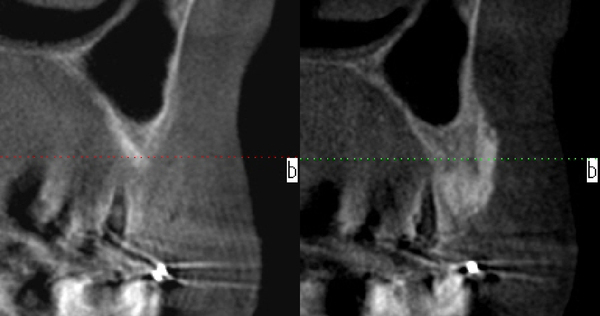

セレックインレーの不適合で虫歯が再発

セレックインレーの破折・ダツリが非常に多いです。出来の悪いセレックインレーが口の中に入っているのをたびたび見かけます。適合の甘いものをセメントでくっつけている。形の悪いものを入れてしまう。

そのせいで磨きにくい状態が出来上がってしまう。その結果、虫歯・再発やダツリを繰り返し歯周病も悪化させてしまうケースが多いです。

適合が悪いため、虫歯が再発 虫歯を取り除き治療終了